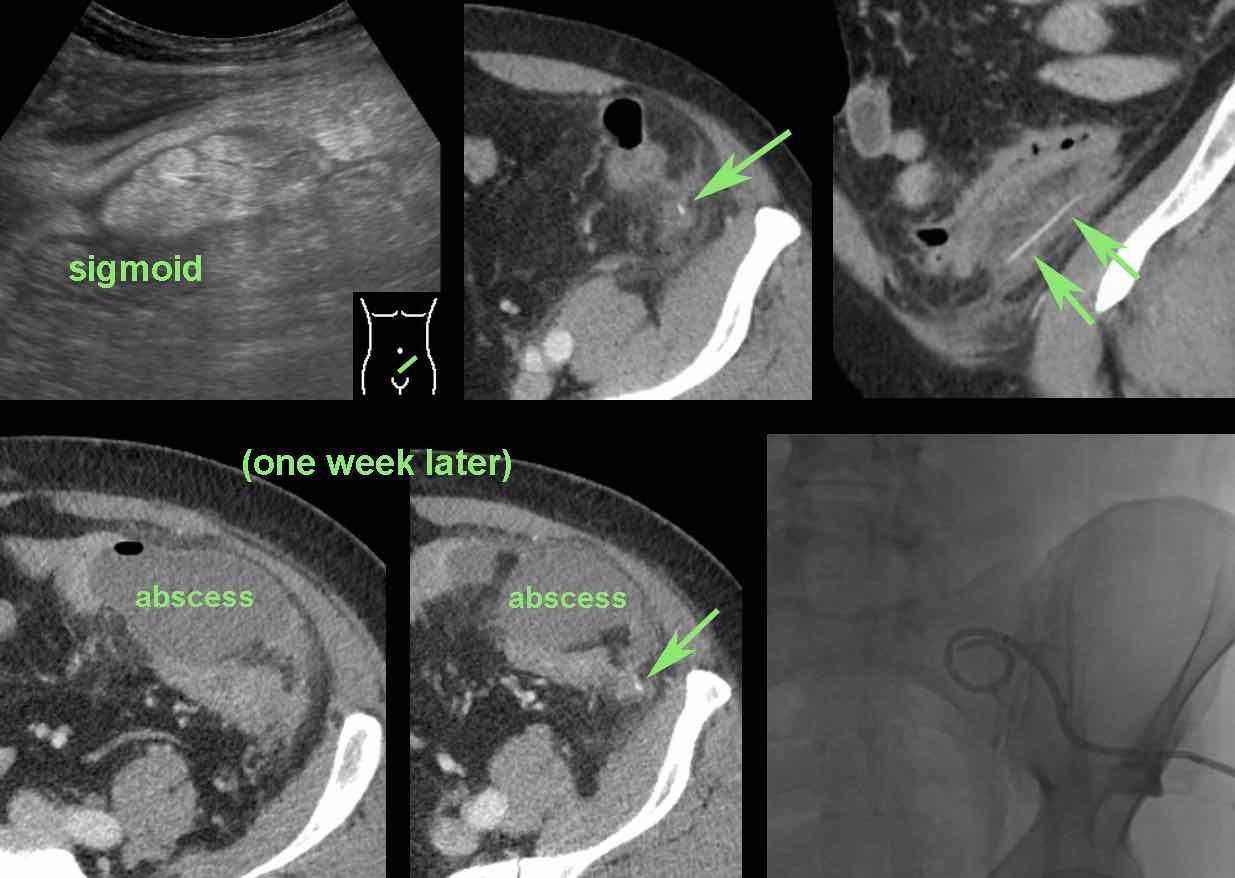

Bệnh nhân nữ người Suriname trẻ (31 tuổi) với đau hố chậu trái 3 tuần và CRP 55, nghi ngờ viêm phần phụ hoặc viêm túi thừa.

Tiền sử vỡ tử cung.

Siêu âm cho thấy khối giảm âm bên trái tử cung (u.) nghi ngờ áp xe vòi trứng-buồng trứng (TOA).

Ở ngoại vi thấy một phản âm mỏng, đường cong (mũi tên).

Siêu âm qua đường âm đạo xác nhận xương cá (mũi tên) trong thành của TOA.

CT không tiêm thuốc cản quang cho thấy TOA có liên quan mật thiết với đại tràng sigma, vốn cũng có dày thành khu trú.

Trong phẫu thuật, TOA và xương cá dính chặt vào đại tràng sigma đã được lấy ra.

Rõ ràng, xương cá sau khi xuyên thủng đại tràng sigma đã di chuyển vào buồng trứng trái, gây ra TOA.

Lưu ý màu xanh lá của xương cá, có thể do sắc tố mật.

Bệnh nhân nữ 74 tuổi nhập viện với đau bụng dưới sâu kéo dài 3 tuần. Xét nghiệm: bạch cầu 15, CRP 150. Bệnh nhân có tiền sử nhiều lần phẫu thuật phụ khoa.

CT được thực hiện và phát hiện một dị vật dạng xương, với cả hai đầu đều có vẻ xuyên thủng đại tràng sigma.

Siêu âm qua đường âm đạo xác nhận dị vật đi xuyên qua lòng đại tràng sigma, do đó có thể lấy dị vật qua nội soi đại tràng.

Trong quá trình nội soi, xương gà phải được bẻ làm hai phần để lấy ra an toàn. Bệnh nhân hồi phục tốt với sự hỗ trợ của kháng sinh.